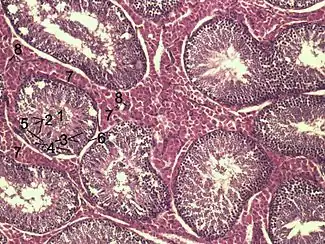

Histological section through testicular parenchyma of a boar. 1 Lumen of Tubulus seminiferus contortus, 2 spermatids, 3 spermatocytes, 4 spermatogonia, 5 Sertoli cell, 6 myofibroblasts, 7 Leydig cells, 8 capillaries